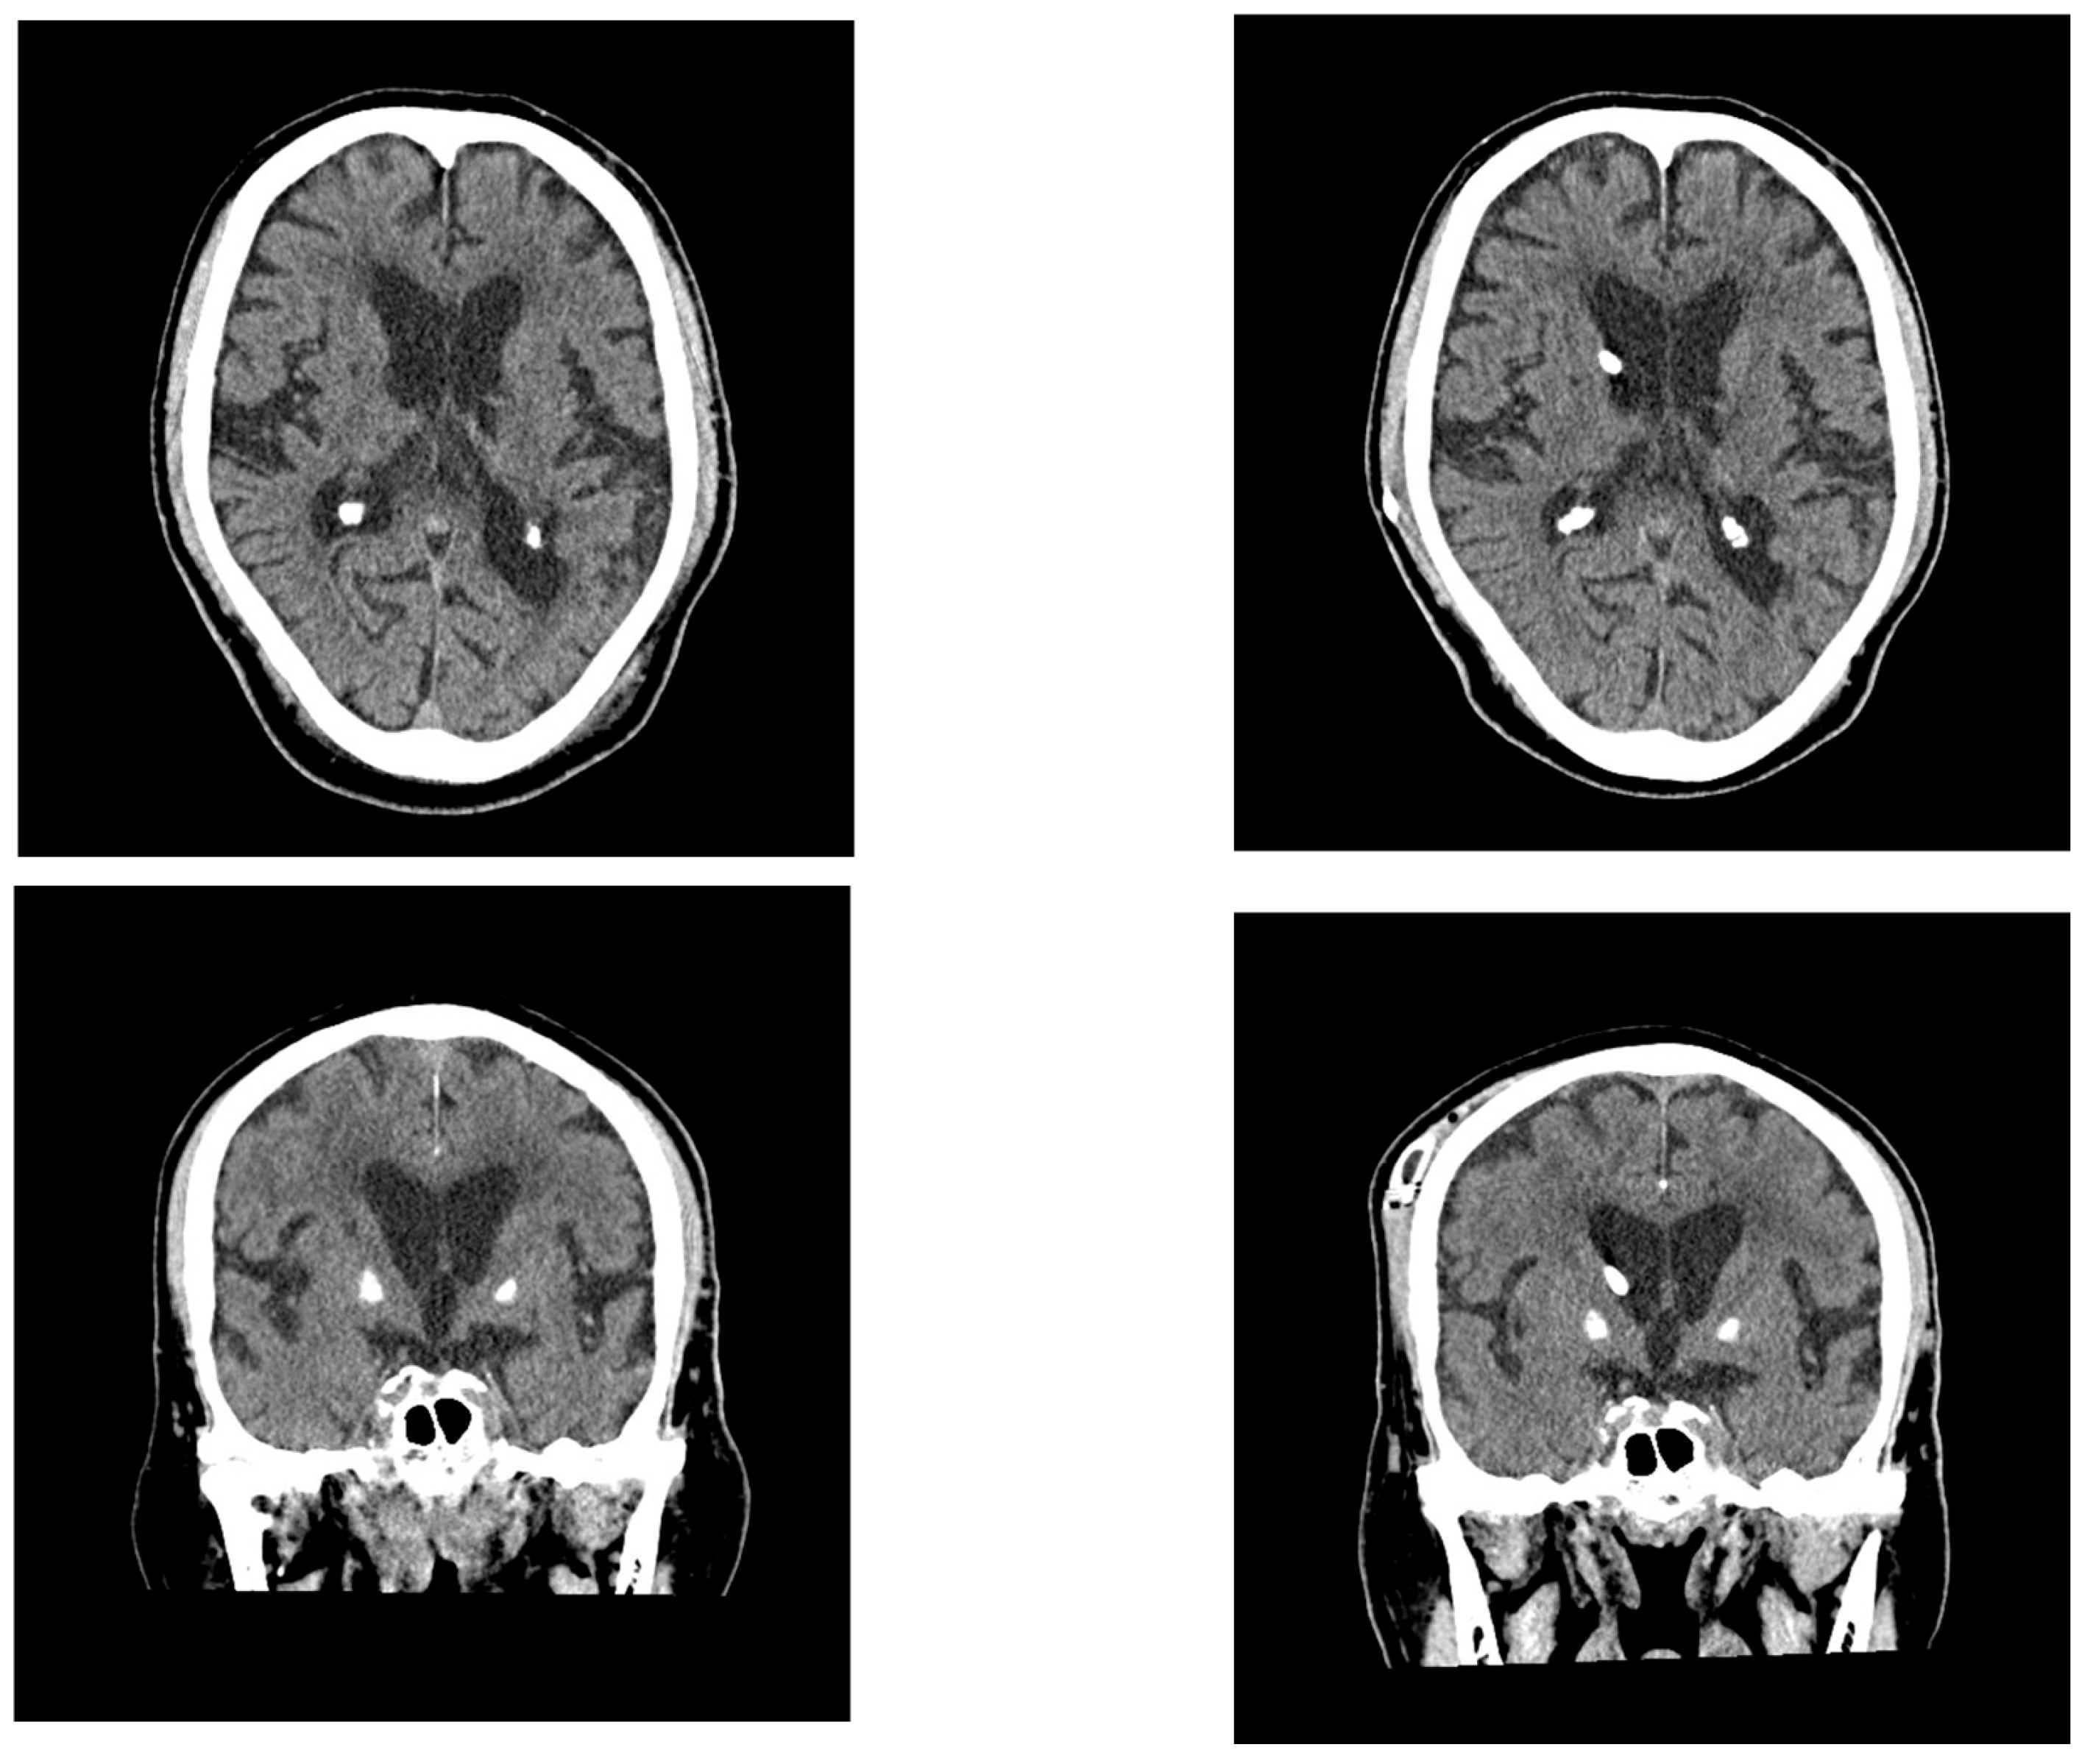

2.2. Case 2